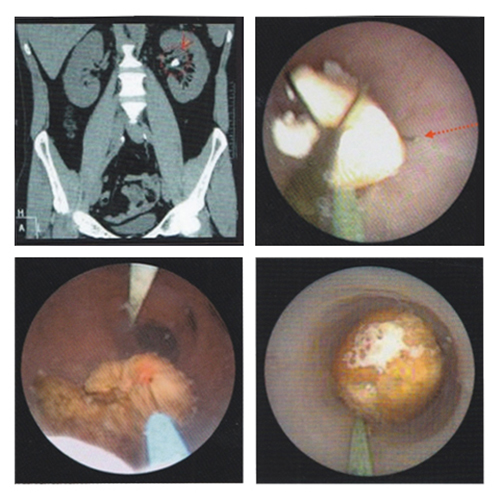

RIRS (Retrograde Intrarenal Surgery)

Treats moderate size renal stone

Flexibility of scope

Evaporates stone in dust

Single sitting

No risk of bleeding

Natural orifice – No incision

Best modality available today

Flexible URS & RIRS

Flexible URS

7FR - 2.3mm thickness

270 Degree Movement

Stone in kidney